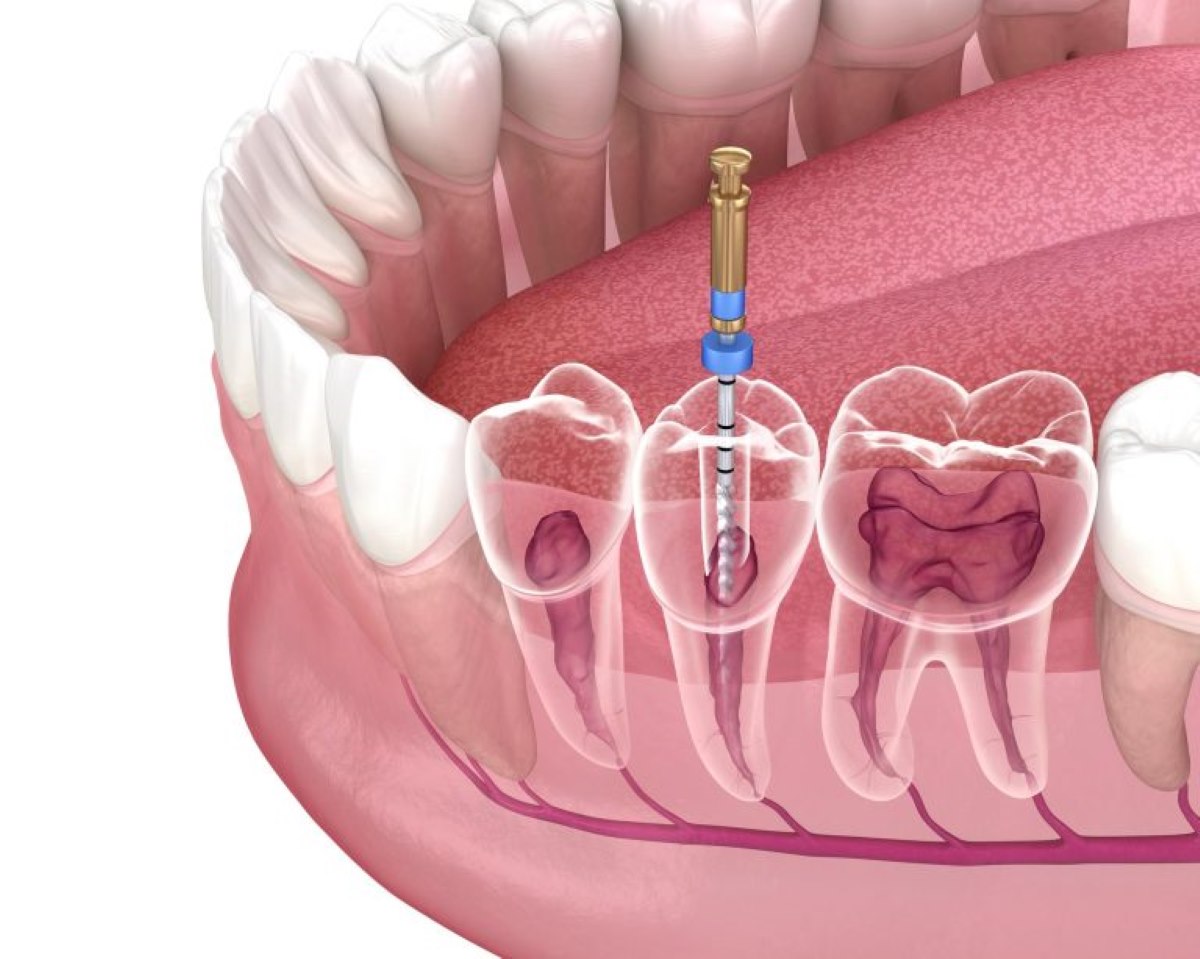

A root canal is a procedure used to repair a severely decayed or damaged tooth. It is also known as endodontic therapy. It entails removing diseased or inflammatory pulp tissue from within the tooth, cleaning and sanitizing the pulp chamber and root canals, and then closing the gap to avoid further infection. The treatment is called after the natural canals found within the roots of teeth.

The most obvious advantage of a root canal is pain alleviation. A strong toothache produced by an infected or inflamed tooth pulp is frequently connected with the operation. Deep decay, a broken tooth, or trauma can all cause the pulp, which includes nerves and blood vessels, to become infected. During this procedure your dentist near you will remove the damaged pulp, relieving discomfort and preventing infection from spreading.

Natural teeth should always be preserved since they perform better than artificial substitutes. A root canal allows you to preserve your natural tooth and prevent extraction. The tooth is cleaned, filled, and sealed after the diseased pulp is removed. This procedure guarantees that the tooth is able to function correctly, allowing for biting, chewing, and good alignment with neighbouring teeth.